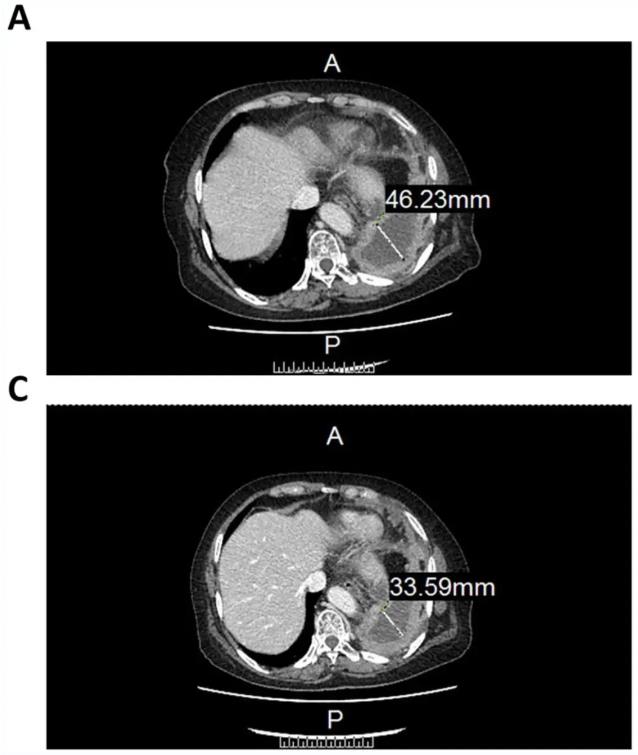

2、患者左肺包裹的胸腔积液,从46.22mm,减少至33.59mm(详见下图)。

▲图源“Sage Journals”,版权归原作者所有,如无意中侵犯了知识产权,请联系我们删除